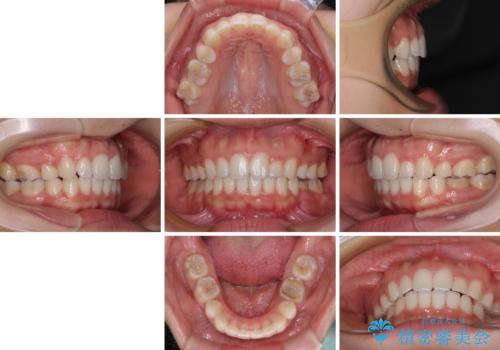

【モニター】閉じにくい口元 ワイヤー装置での抜歯矯正

- 20代女性

- 審美装置

- 2年2ヶ月

- 咬み合わせと口元の突出感を気にして来院された患者様です。

上顎に対して、下顎が後方にある咬み合わせであるため、上顎左右小臼歯のみの抜歯か、下顎左右小臼歯も抜歯とするのか悩むところでした。

まずは上顎のみ抜歯を行って矯正治療を進め、下顎小臼歯も抜歯が必要となれば速やかに抜歯することとしました。

上顎抜歯のみでは奥歯の咬み合わせを改善することが困難であったため、途中で下顎小臼歯も抜歯をしました。

抜歯のタイミングが遅れると治療期間が長期化するため、速やかに抜歯の判断をし、2年強の期間で治療を終えることができました。